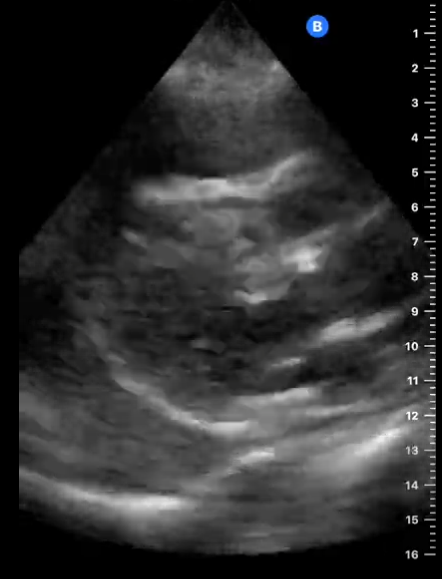

En la ecocardiografía se aprecia latido cardiaco con intercambio de flujos muy disminuido y el miocardio movilizándose en el interior del derrame pericárdico contenido sin taponamiento.

La radiografía torácica mostró una imagen de corazón en «tienda de campaña» típico de derrame pericárdico, por su parte el electrocardiograma mostraba ondas con bajo voltaje y aunque era rítmico, apenas eran apreciables las ondas P. el TAC de tórax confirmó el diagnóstico de derrame pericárdico.

En este caso tenemos un cuadro de derrame pericárdico con repercusión hemodinámica pero apreciándose latido cardíaco y suficiente contractilidad como para no incurrir en taponamiento cardíaco que hubiera supuesto una emergencia vital para la paciente.